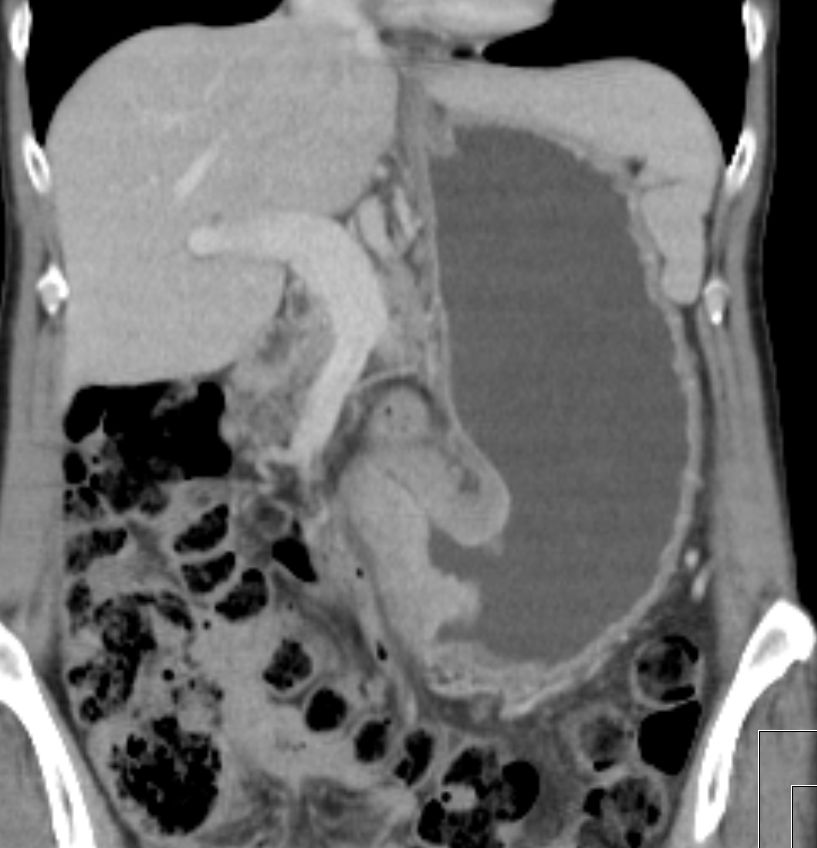

| Magenantrum | Obstruierendes Magenantrumkarzinom. Ausgedehnte Lebermetastasen.![]() | |||